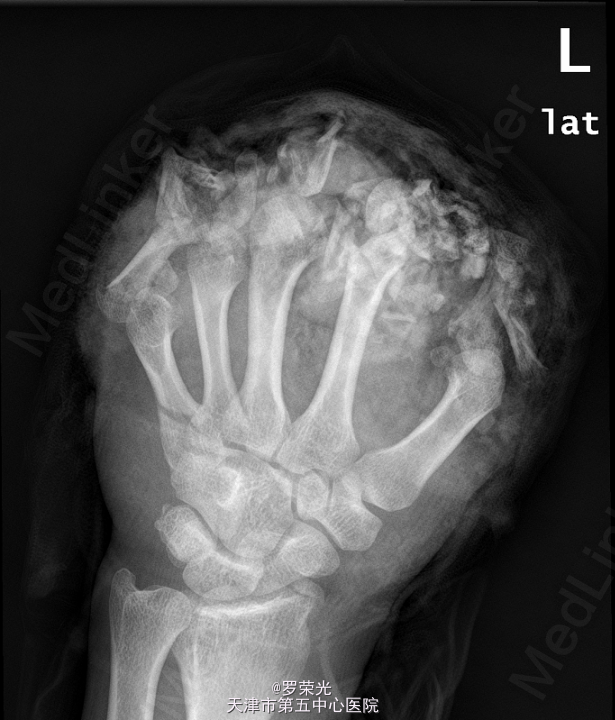

患者,男,30岁,因“左手毁损1月余”入院。

查体:左手远端腹部带蒂皮瓣移植术后,皮肤色泽无殊,未见明显渗出,无红肿疼痛,可触及骨擦感,桡动脉搏动有力,左手活动固定,生理反射存在,未引出病理反射,余肢体末梢血循、感觉、活动正常。本院 X线:左手多发指骨骨折,多发指骨及关节结构显示不清,第2掌骨远端结构欠清,大部指骨缺如或仅剩骨碎片影,周围软组织亦缺如,第5掌骨近段亦见骨折,断端对位尚可;左腕关节在位;附见:左桡骨远端见游离骨片影,考虑骨折。